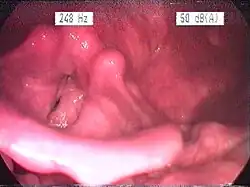

Laryngitida je odborný název pro zánět hrtanu.

Mezi hlavní příznaky laryngitidy patří štěkavý kašel, bolesti v krku, chrapot nebo úplná ztráta hlasu. Onemocnění nastupuje velmi rychle (obvykle v noci) a může být doprovázeno vysokou horečkou.[1] Laryngitidu diagnostikuje lékař pohledem do krku, kde je vidět zduření hlasivek a sliznice hrtanu. Zvláště u dětí může být onemocnění nebezpečné. Otok hrtanu může způsobit dušení a je třeba okamžitě vyhledat lékařskou pomoc.[2]